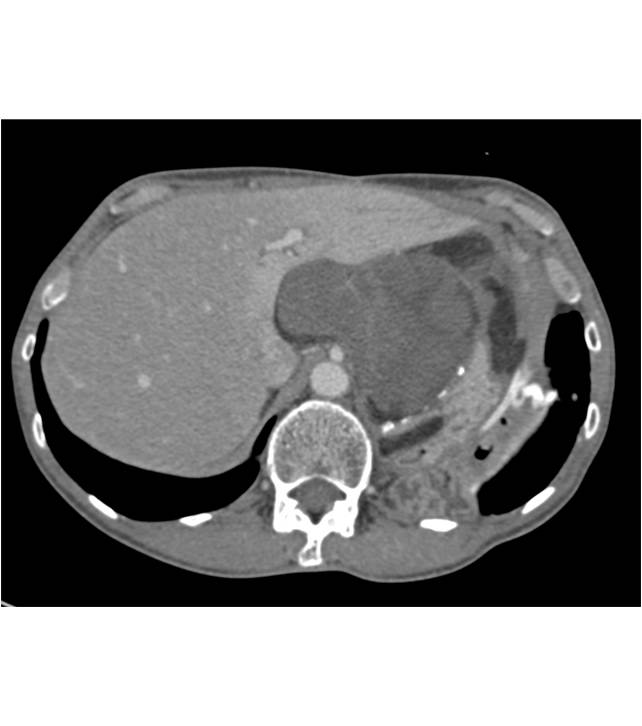

Duodenal Carcinoma